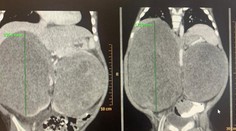

Zdravie Extrémne náročné operácie sa podarili: Chlapcovi v Bratislave odstránili dva veľké obojstranné nádory na obličkách TASR 25. 9. 2022